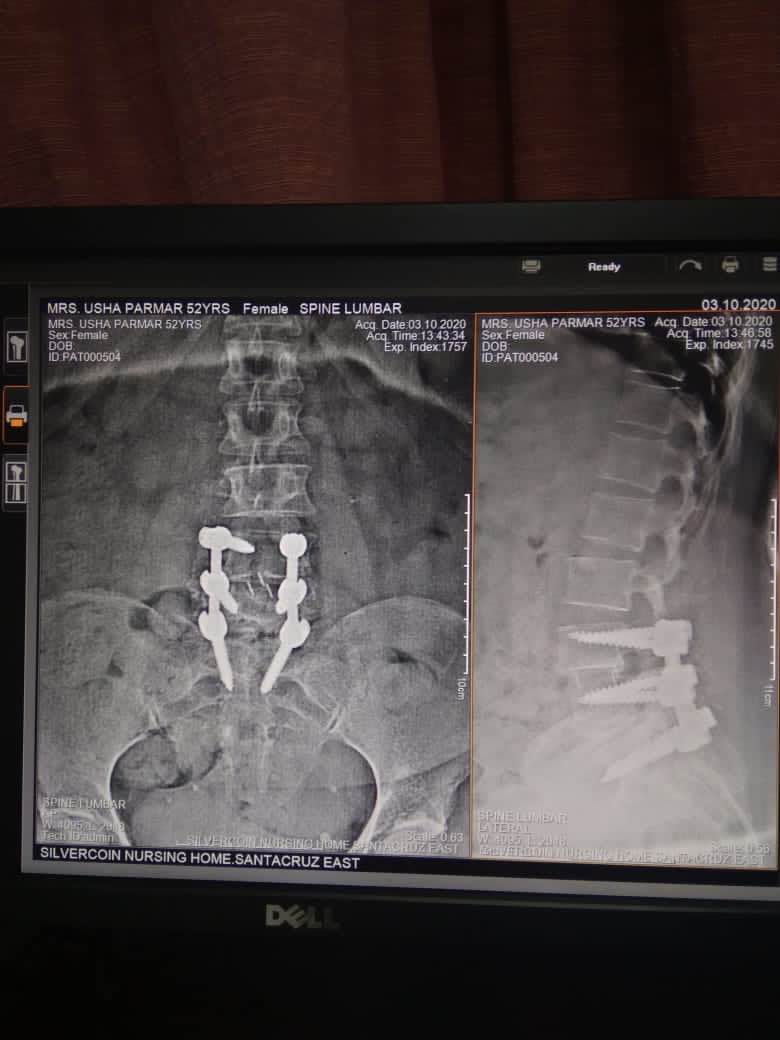

Best SPINE SURGEON IN ANDHERI